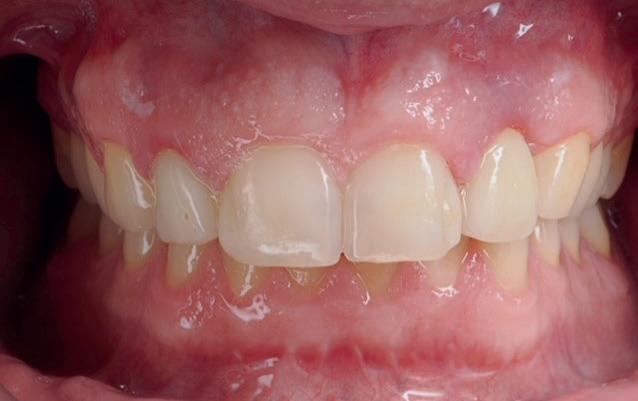

Implantologische behandelingen in het esthetische front vragen meer dan technische vaardigheid alleen. Ze vragen om overzicht, timing, vertrouwen en een team dat als vanzelf samenwerkt onder druk. Juist bij complexe casussen, waarin angst, infectie en hoge esthetische verwachtingen samenkomen, wordt zichtbaar hoe bepalend de rol van de tandartsassistent is.

Deze casus beschrijft een uitgebreide immediate implantaatbehandeling bij een patiënt die door meerdere collega’s werd geweigerd. Niet omdat de mogelijkheden ontbraken, maar omdat de complexiteit vroeg om een perfect afgestemde samenwerking. Het verhaal laat zien hoe de assistent in zo’n traject veel meer is dan een uitvoerende kracht of “mal”, maar een dynamische surgical guide die het proces mede stuurt, bewaakt en mogelijk maakt.De patiënt: wanneer alles samenkomt

In de prothetische fase (zie foto’s) is in de bovenkaak gebruikgemaakt van verschroefde zirconia bruggen, die enkel buccaal zijn opgebakken. Deze bruggen zijn verlijmd op individuele, geanguleerde titanium abutments. In de onderkaak is een verschroefde kunststofbrug op een titaniumbasis (wrap-around) gemaakt. Voor deze combinatie is gekozen vanwege een minder hinderlijk tikkend geluid bij functie en kleinere kans op breuk van de keramiek. Een nadeel is verhoogde slijtage van de kunststof elementen, maar deze zijn in de jaren later eenvoudig te vervangen op de bestaande brug. Ondanks alle digitale mogelijkheden is de afdruk en registratiefase analoog uitgevoerd, omdat in ervaring van de behandelaren dit bij deze totale rehabilitaties op implantaten nog altijd de grootste precisie oplevert. Er is afgedrukt met impregum in individuele lepels en de pasvorm is gecontroleerd met rigide duralay bars. De relatie wordt vastgelegd zoals bij een volledige prothese met waswallen en pijlpuntregistratie. De opstelling in was wordt gepast en laatste correcties worden gemaakt in samenspraak met de patiënt, de restauratieve tandarts en de tandtechnicus. Na het vastzetten van de suprastructuren worden de schroefgaten afgesloten met composiet.

in de zes maanden bij de mondhygiënist voor peri-implant reiniging, pocketmetingen, mondhygiëne instructies en controles. De AirFlow wordt daarbij standaard gebruikt. Verder wordt de patiënt na één, drie en zes jaar gezien voor controle van de suprastructuren door de restauratieve tandarts. Uit de röntgenfoto’s kan afgeleid worden dat het botniveau gelijk blijft over tijd. Klinisch ziet de situatie er infectievrij uit; de patiënt onderhoudt het zelf netjes met ragertjes, een elektrische tandenborstel als ook de Waterpik.

Patiënt G. is van ver gekomen. Voor het behandelplan was interdisciplinair overleg en samenwerking essentieel om tot het gewenste resultaat te kunnen komen. De Kliniek voor Parodontologie Amsterdam (KVPA) - met ruim 40 jaar ervaring op het gebied van implantologie, restauratieve tandheelkunde, parodontologie, endodontologie en gnathologie - is hiervoor de uitgelezen kliniek. En waar het uiteindelijk om draait: de patiënt is tevreden met het behaalde resultaat!